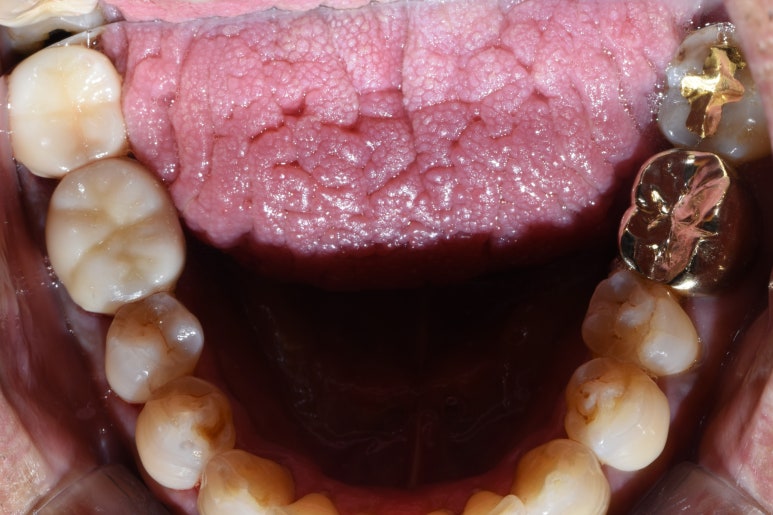

CASE 1. 지르코니아 크라운과 골드크라운 외형 비교

[환자분께서 사진 공개에 동의하셨습니다]

저희 치과에서 지르코니아크라운을 하신 분 중

반대쪽은 다른 치과에서 하신 금이 있는 분이 있어

비교를 위해 사진을 넣어보았습니다

왼쪽 끝 두 치아는 지르코니아 크라운, 오른쪽 두 치아는 금으로 치료되어있는 상태

금으로 하신 부위는 입을 벌려서 웃거나 말할 때 티가 날 거구요,

치아색으로 하신 부위는 입을 벌려서 웃거나 말할 때 많이 티가 나지 않겠죠.